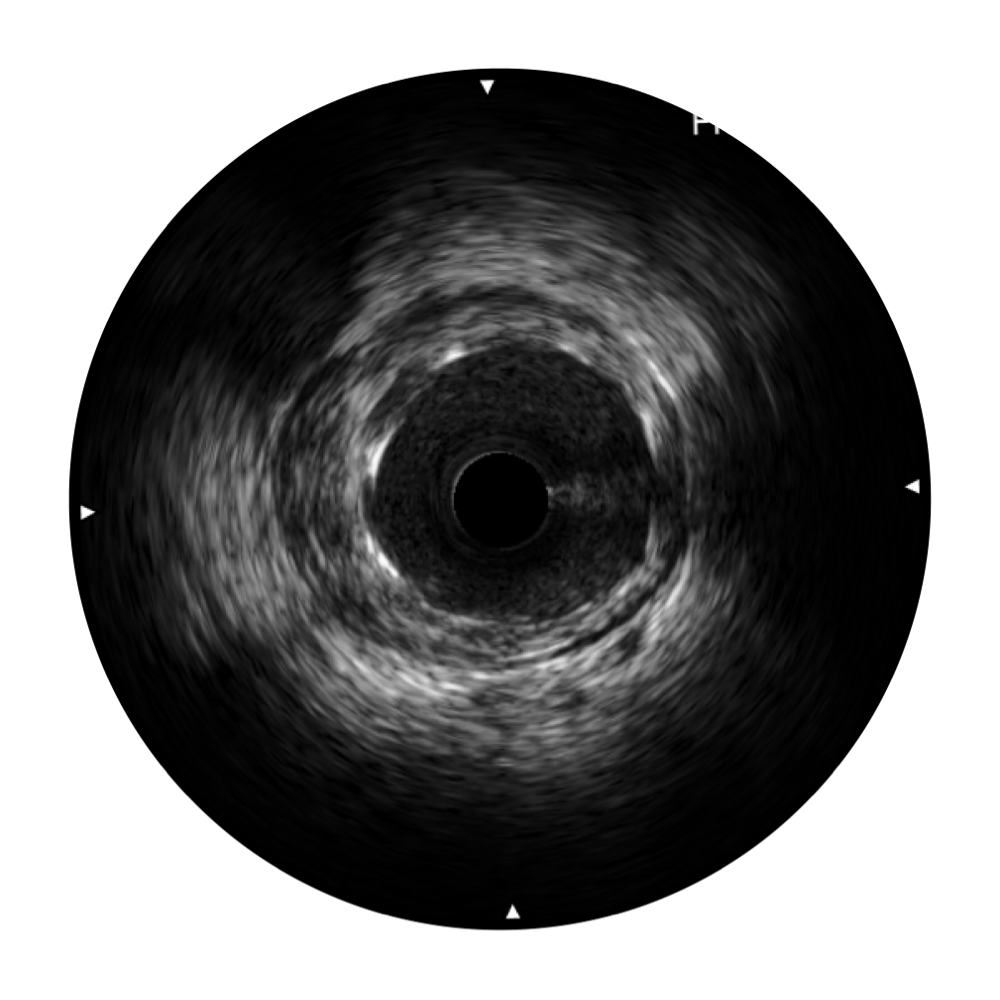

银河集团官网宽频IVUS图像

对比传统IVUS导管成像,银河集团官网宽频IVUS图像的近场支架梁显影更细腻,远场中膜外血管仍清晰可辨,兼顾远中近,兼顾分辨力与穿透深度